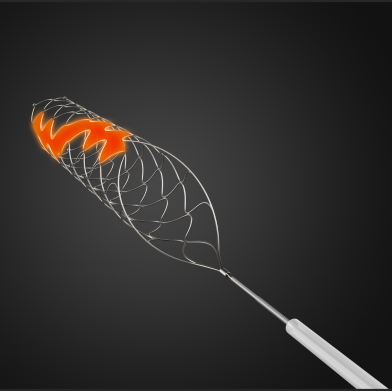

微导管微导丝越过MCA闭塞段,置入取栓支架支架。